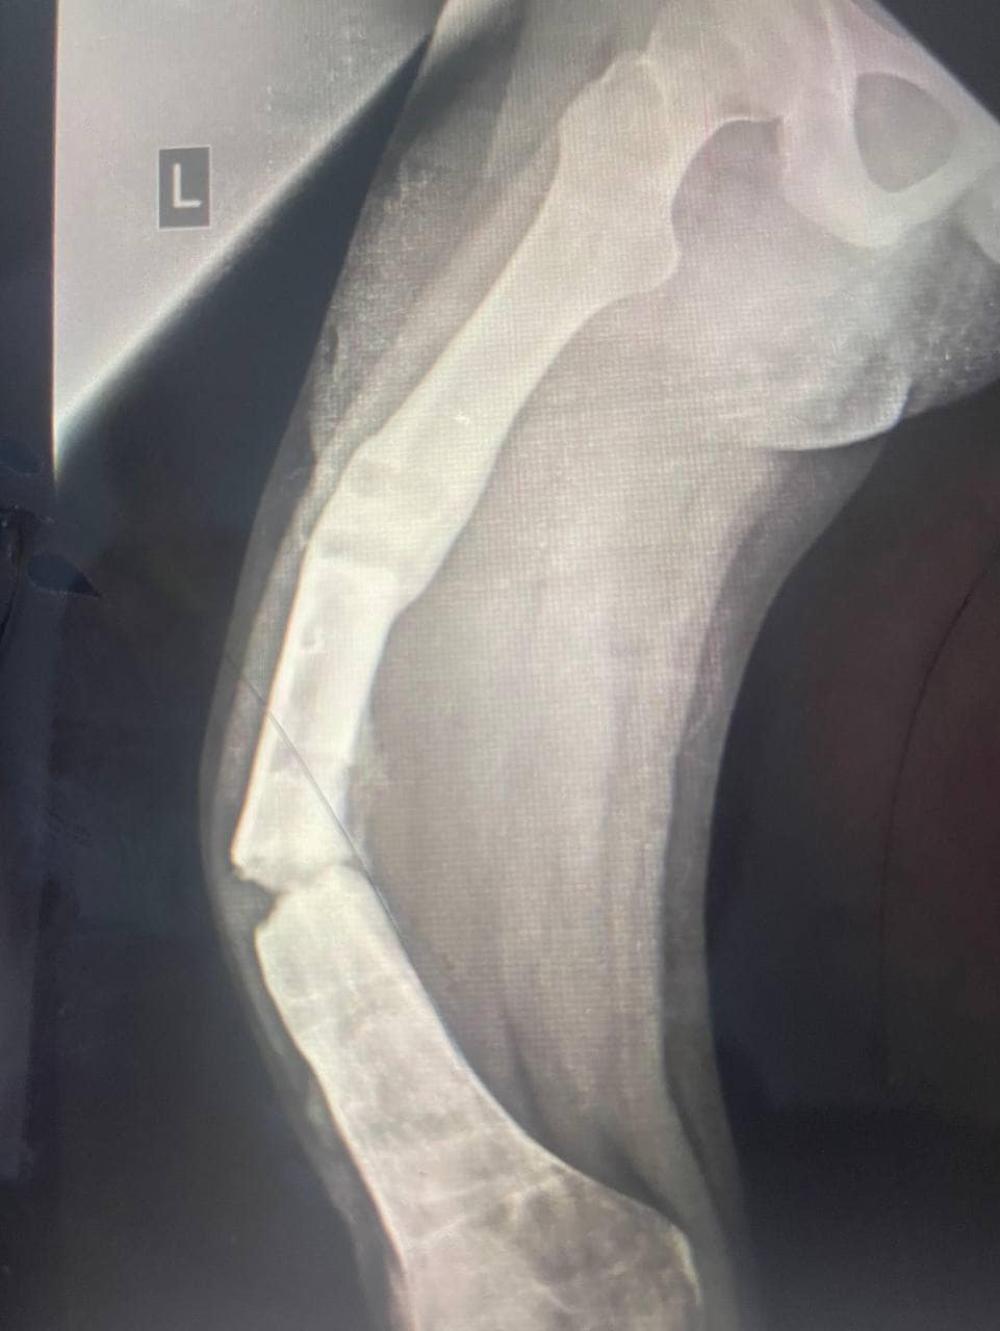

17-річна Ангеліна звернулася до медиків Рівненської обласної дитячої лікарні після невдалого лікування деформації стегна та колінного і гомілковостопного суглобів апаратом зовнішньої фіксації в одній із лікарень України. У результаті пацієнтка отримала значну деформацію кістки та незрощення ділянок від попередніх втручань.

Уже в Рівному в ортопедо-травматологічному центрі розробили індивідуальний план лікування. І в червні провели першу операцію, під час якої в стегнову кістку було встановлено БІОС систему. А у серпні було - другу: корегуючу остеотомію великогомілкової кістки з фіксацією пластиною.

"Завдяки професіоналізму лікарів та сучасним технологіям, всього за 4 місяці ми змогли поставити дівчину на ноги! Адже протягом останніх двох років пацієнтка самостійно не пересувалася, нога була не опорною", - потішили результатом медики.